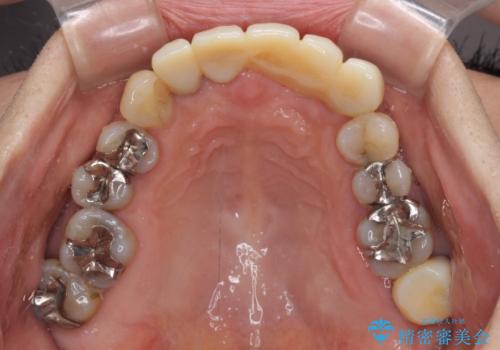

- 前歯の歯肉の腫れを気にして来院された患者様です。

前歯のみならず、奥歯の銀歯や下顎前歯のデコボコなど、色々と気になる部分を治したいとのことでした。

前歯は抜歯が必要であったので、抜歯を行い、その後歯肉移植をおこなった上でオールセラミックブリッジによる補綴治療を行うこととしました。

下顎と上顎臼歯部については矯正治療を行い、奥歯の欠損部位はオールセラミックブリッジを、その他の銀歯はセラミックインレーなどにより治療を行うこととしました。